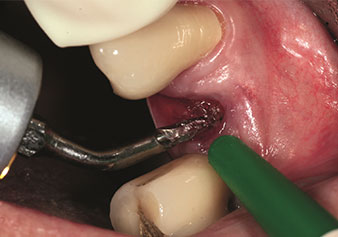

Sıklıkla hafife alınan uygulamalardan biri, alveolar yönetimin bir parçası olarak diş köklerinin veya kök parçalarının nazikçe çıkarılmasıdır. Şu anda iki modeli (W&H'ten EX1 ve EX2) mevcut olan hassas periotomlarla, özel olarak endodontik ön işleme tabi tutulmuş dişler veya ankilozik kökler de kolayca çıkarılabilir. Sonuç, sert ve yumuşak dokuları tamamen sağlam olan ekstraksiyon alveolleridir, çünkü genellikle onları açmak gerekli değildir.

Bu, daha sonra veya hemen implant bakımı için optimum bir temel oluşturur [şekil 1 ve 2, Dr. Torsten Conrad’ın (Bingen a. Rhein) onayı ile kullanılmıştır].

Fotoğraf: © Dr Torsten Conrad (Bingen a. Rhein)